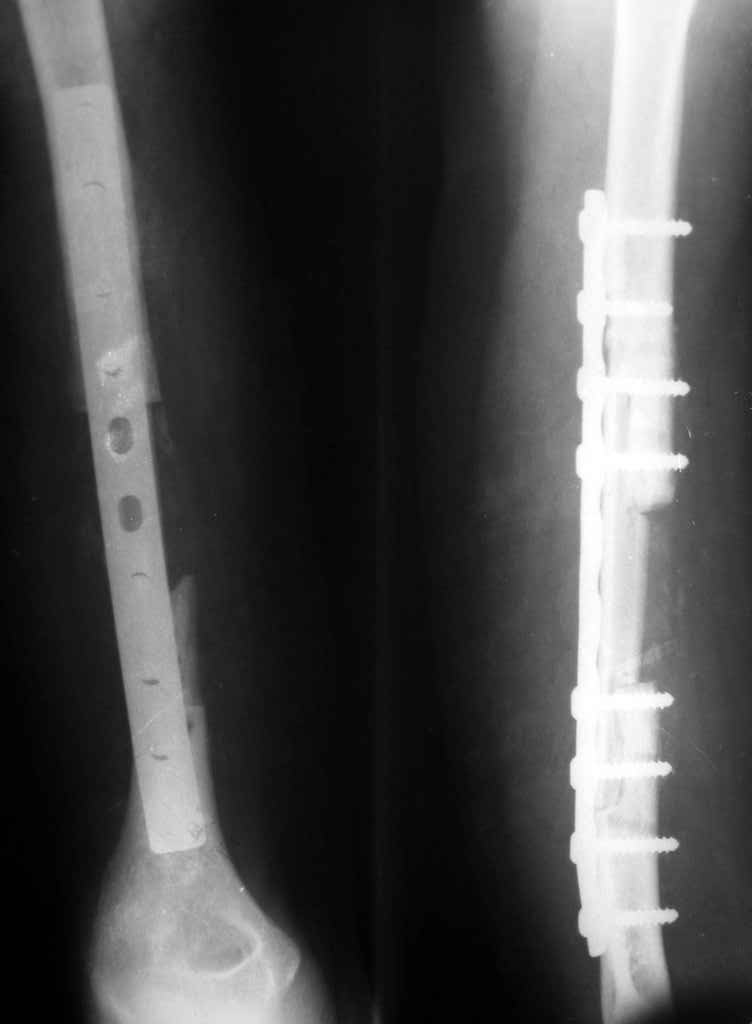

был ли остеосинтез с диастазом - неизвестно, но неадекватность фиксации пластиной достаточно очевидна.

1 пластина тонкая

2 всего 6 шурупов через пластину - для плеча это минимальное требование при свежем переломе

3 проксимальный фрагмент на момент ( или в ходе) второй операции был расколот , о чем свидетельствует наиболее проксимальный lag screw, то есть прокс 3 шурупа через пластину были введены в расколотый фрагмент. Неудивительно, что пластину вырвало